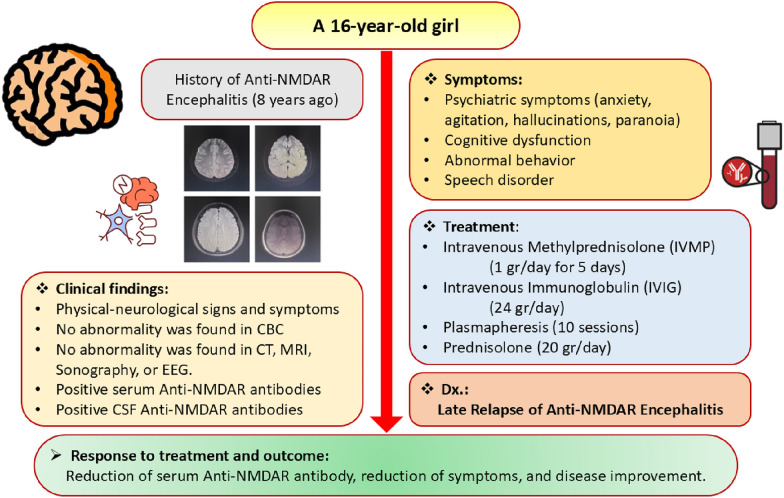

In this case study, we report on a 16-year-old Iranian female experiencing a relapse of anti-N-methyl-d-aspartate receptor encephalitis 8 years after her initial diagnosis. She was admitted to the hospital with dysphasia (a speech disorder) and dyslexia (reading and writing impairment). A thorough clinical evaluation revealed the presence of anti-glutamate receptor type N-methyl-d-aspartate receptor antibodies in her serum and cerebrospinal fluid, confirming the diagnosis. Following treatment with immunotherapy and plasmapheresis, she made a complete recovery.

A 16-year-old Iranian female was brought to the hospital by her parent with a chief complaint of progressive speech impairment over the past 2 weeks. Initially, she experienced difficulty pronouncing certain letters, which worsened to intermittent stuttering during verbal communication. Over time, she also exhibited impairment in reading and writing. Concurrently, her parents noticed emotional instability, atypical behaviors, and a decline in interest. She occasionally displayed disorientation to time and place, affecting her judgment. Additionally, she developed delusional thoughts, mistaking her imagination for reality, causing significant anxiety.

Although the patient had no relevant family history of neurological or psychiatric disorders, she had a significant past medical history. Her parents stated that, 8 years ago, she experienced similar symptoms to her current presentation, which included a seizure. After a comprehensive examination, she was diagnosed with anti-N-methyl-d-aspartate receptor (NMDAR) encephalitis. Then, she was treated with high-dose corticosteroids, immunotherapy, plasmapheresis, and plasma exchange, leading to a complete recovery without lasting neurological issues.

The patient underwent detailed neurological and physical examinations by a specialist. Significant findings included neurological symptoms such as altered mental status, agitation, paranoia, hallucinations, and mood swings. Physical assessments revealed movement disorders such as facial twitching, involuntary writhing, and abnormal muscle contractions, leading to unusual postures. Initially, she exhibited generalized hyperreflexia and increased muscle tone. Cognitive tests showed fluctuating consciousness levels and impaired executive function. Throughout her hospitalization, she developed limb dystonia, indicating advancing neurological impairment.

Paraneoplastic antibodies and an autoimmune panel (ANCA-c, ANCA-p, anti-phospholipid IgG, anti-NMO, anti-SSA/Ro, anti-SSB/La, anti-dsDNA) were negative, and only serum anti-NMDAR antibodies showed a positive result.

The cerebrospinal fluid (CSF) analysis revealed a slight elevation in white blood cells (pleocytosis) and protein levels but no other significant abnormalities. Notably, the CSF tested positive for anti-NMDAR antibodies, with a titer level of 1000, confirming the presence of these antibodies in the nervous system (Table 1).

The MRI findings were normal, but several diffuse cortical hyperintensities were observed, consistent with the patient’s history of anti-NMDAR encephalitis. This may indicate an inflammatory process related to a relapse. However, the overall normal findings and the absence of abnormalities in complementary imaging studies, including brain CT, chest X-ray, and ultrasounds, suggest no concurrent structural or systemic pathology. The EEG was also evaluated and found normal (Figs. 1, 2, 3).

Finally, on the basis of the clinical findings (signs and symptoms, medical history of patients), medical imaging results, and laboratory findings (antibodies detected in the serum and CSF, blood analysis), this patient was diagnosed with “late relapse of anti-N-methyl-d-aspartate receptor (NMDAR) encephalitis.”

The patient underwent treatment with a combination of immunotherapy, symptomatic management, and supportive care. Immunotherapy reduces inflammation and modulates the immune system.

As the first line of treatment, she received intravenous methylprednisolone (IVMP) and intravenous immunoglobulin (IVIG) for five consecutive days. After being administered these drugs for 5 days, the patient was only slightly better, but there was no satisfactory improvement in her symptoms.

Plasmapheresis

The patient underwent 10 plasmapheresis sessions—initially, 5 sessions were administered daily, followed by 5 sessions spaced every other day—to help remove the harmful NMDA antibodies from her serum. Her vital signs and overall condition were carefully monitored throughout each session to ensure her safety. After the sixth session, her symptoms showed some improvement. We also conducted blood tests before and after each session to track the treatment’s effectiveness and monitor her electrolyte levels. Following each session, the patient was observed for any immediate adverse effects, such as low blood pressure, bleeding, or allergic reactions. Her neurological status was regularly assessed, and laboratory tests, including antibody titers and imaging, were used to evaluate her prognosis.

As part of her treatment, she also received a low-dose prednisolone at 20 mg per day, which was gradually reduced by 5 mg each week over the course of a month and then discontinued. The patient tolerated the treatment well, with no adverse effects observed.

Follow-up of the patient

After the patient was discharged from the hospital, her neurologists and immunologists regularly followed up with her. She underwent periodic neurocognitive assessments to evaluate her recovery and her need for continued rehabilitation. Additionally, her CBC, LFT, and RFT were periodically monitored. Finally, her serum anti-glutamate receptor NMDA decreased, and the symptoms and signs improved ultimately approximately 40 days after starting the treatment. Figure 4 demonstrates a summary of this female patient.